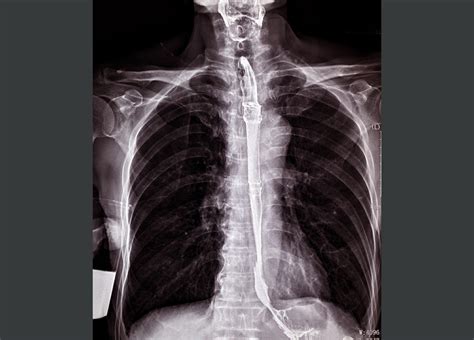

The placement of a stent in esophagus is generally performed by a gastroenterologist or a specialized thoracic surgeon. The procedure is typically minimally invasive and is conducted under sedation or light anesthesia.

1. Endoscopic Guidance: The doctor inserts an endoscope—a thin, flexible tube with a camera—down the throat to visualize the narrowed area.

2. Measurement: Using X-ray imaging (fluoroscopy) or direct visual inspection, the physician measures the exact length and width of the obstruction to select the appropriately sized stent.

3. Deployment: The stent is loaded onto a delivery system and guided into the esophagus. Once positioned correctly across the blockage, the stent is deployed, where it expands against the esophageal walls.

4. Verification: The physician confirms the stent is properly seated before removing the delivery catheter.